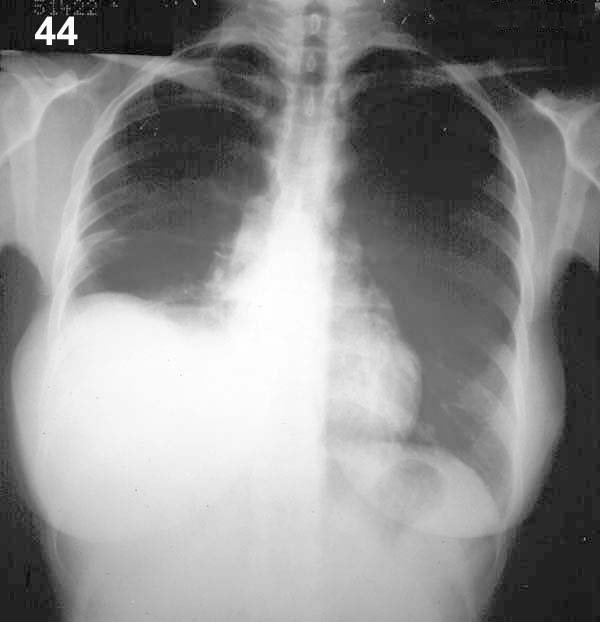

Esquema 44 Comentario placa 44 La primera impresión es que el diafragma derecho se encuentra ascendido. Sin embargo, la historia del paciente y el desplazamiento del vértice de la supuesta cúpula diafragmática hacia la pared lateral del tórax, hicieron sospechar un derrame infrapulmonar. La cúpula del diafragma alcanza su mayor altura a nivel de la linea medioclavicular. Para comprobar esta hipótesis se tomó una radiografía en decúbito lateral con rayo horizontal (placa 45). |